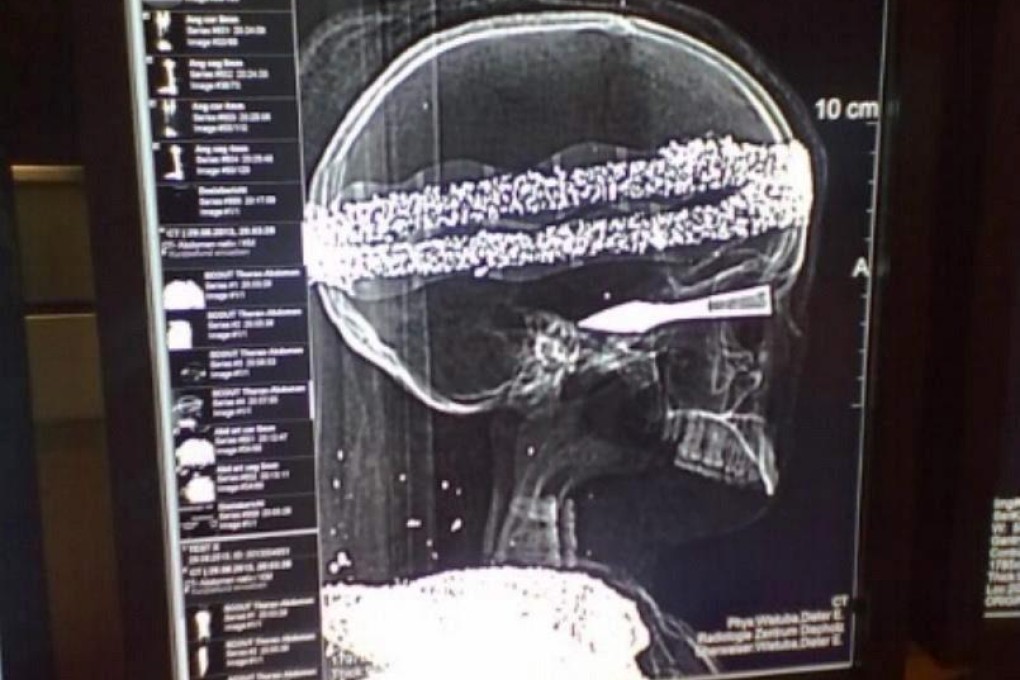

Adding to the riddle is a death mask also found in the box, and the fact that X-rays show a metal layer covering the bones of the 1.49-metre-long human remains of unknown gender.

Pathologist Andreas Nerlich of Munich's Bogenhausen hospital said that, while the skull and the bones are real, the mummy is "a fake, made from one or several human bodies".